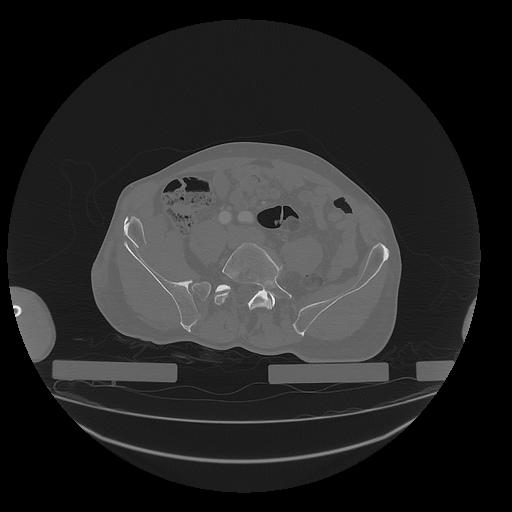

31 PULMON,CE,Vol,1.0,PULMON,,